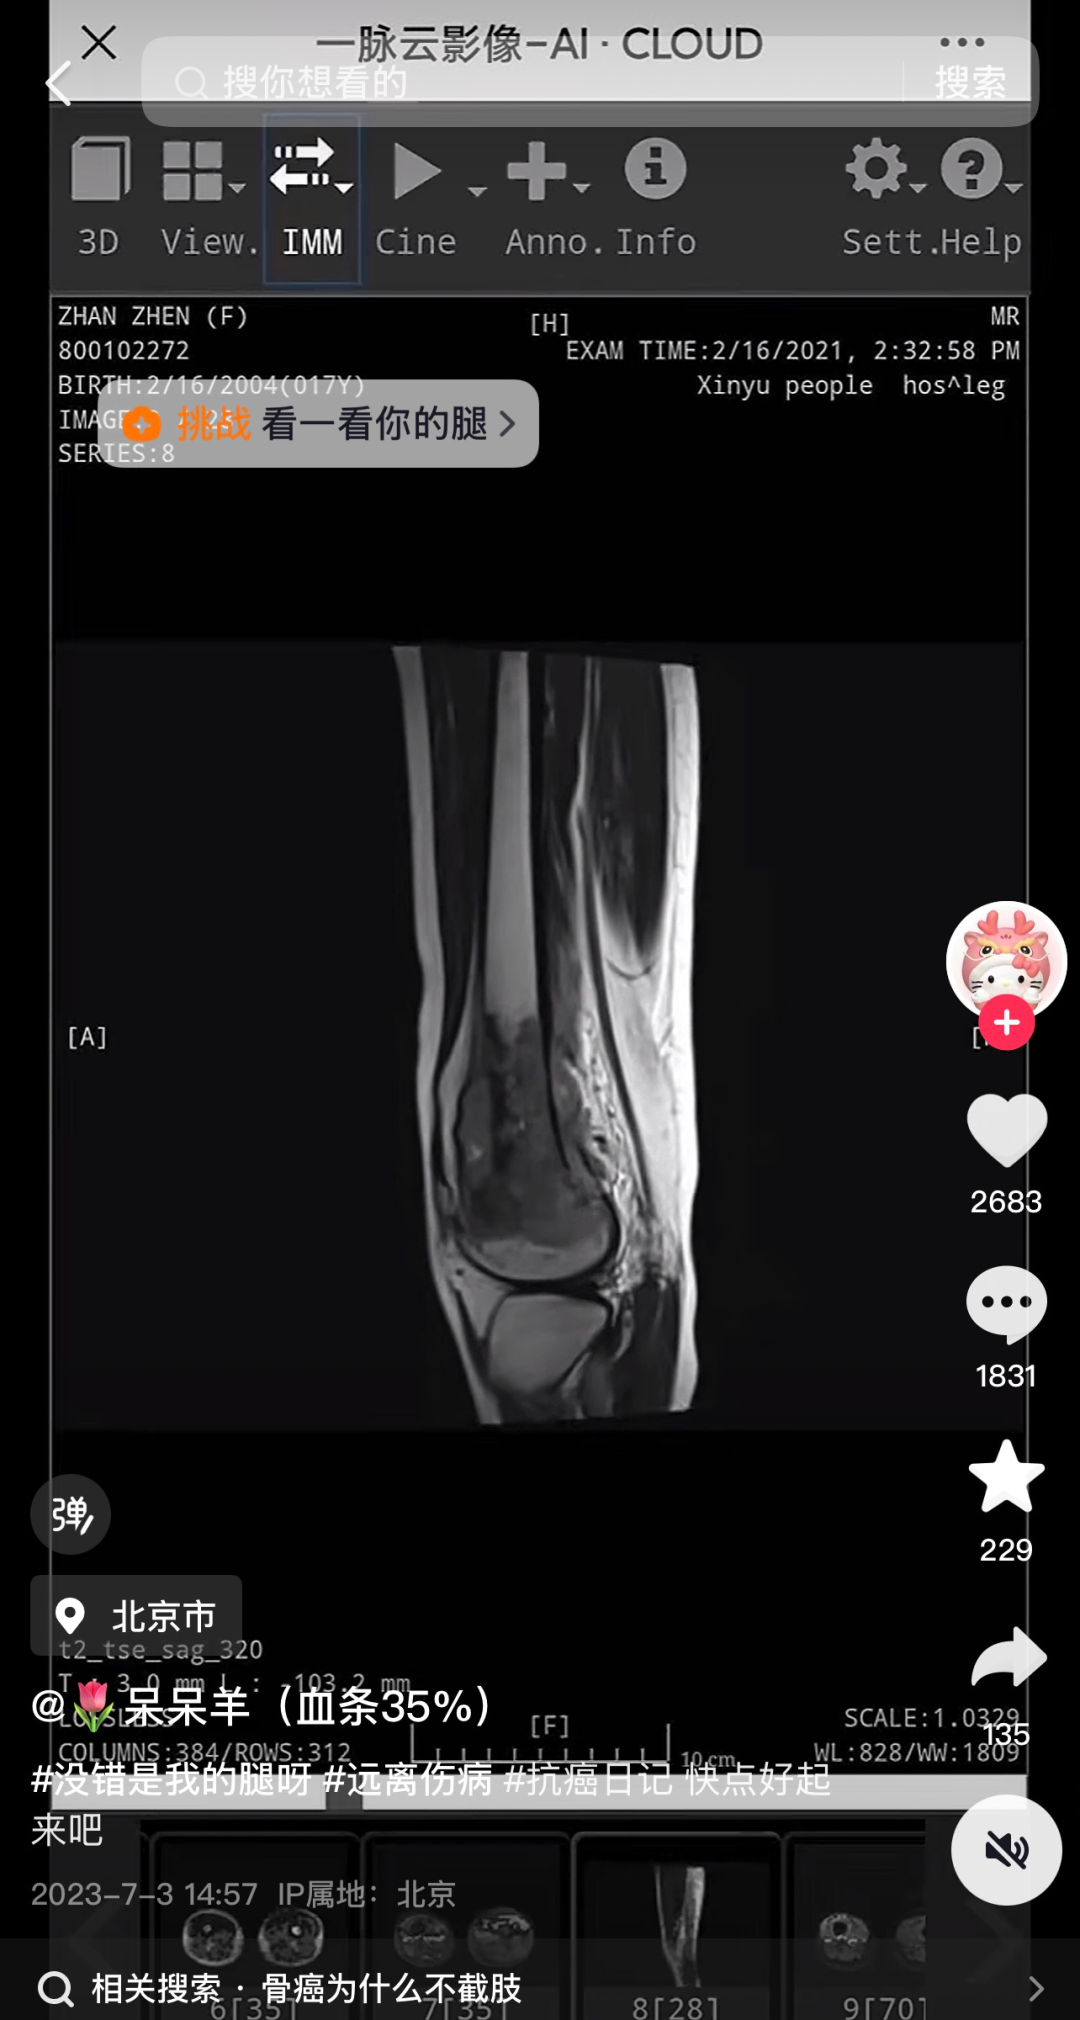

记者发现,网红“呆呆羊(血条35%)”短视频账号有16.7万粉丝,2023年7月3日,“呆呆羊”更新首条内容,视频中“呆呆羊”发布了自己的诊断报告,时间为2021年2月16日。

在之后的两年更新时间里,“呆呆羊”账号大部分作品是自己的抗癌视频。据悉,“呆呆羊”5年经历了40次化疗、20次放疗、25次免疫治疗、多次插管,长期卧床与死神擦肩。其最后一条视频停留在7月15日,多名网友在账号视频下留言表达哀思。

Her account had over 167,000 followers. Since July 2023, she shared her cancer journey, including her 2021 diagnosis. Over five years, she documented her treatments — 40 rounds of chemotherapy, 20 radiation sessions, 25 immunotherapy treatments — and her gradual decline. Her final video was posted on Tuesday, three days before she passed.